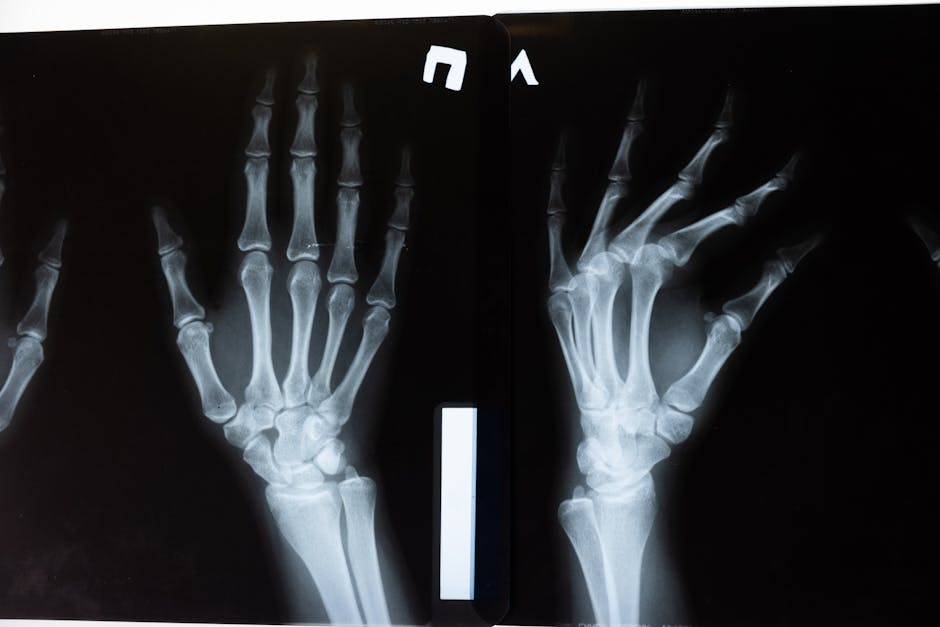

- Wrist and forearm fractures are common “defensive” injuries when people reach out to break a fall.